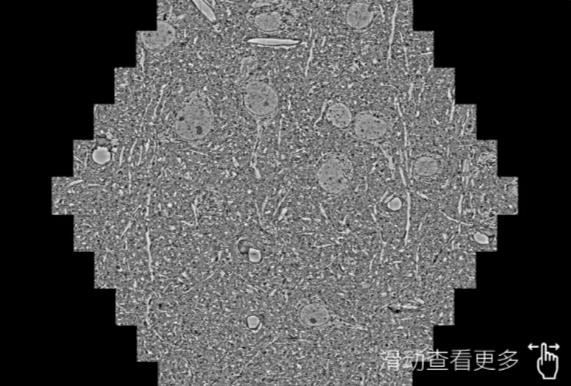

鼠脑切片。左图使用张家口蔡司张家口扫描电镜MultiSEM706对165μmx143pm面积区域成像,耗时仅需1.5秒。右图为鼠脑切片中30μm区域放大效果。样品由芝加哥大学B.Kasthuri提供。

使用蔡司高速张家口扫描电镜MultiSEM对1mm²人脑皮层组织进行高分辨成像,并对其中的各种细胞结构进行三维重构分析。左图展示了2x3mm²组织平面中锥体神经元的三维重构效果。右图显示了局部体积神经元三维重构。图像由哈佛大学chtman实验室提供,渲染图由D. Berger 制作。